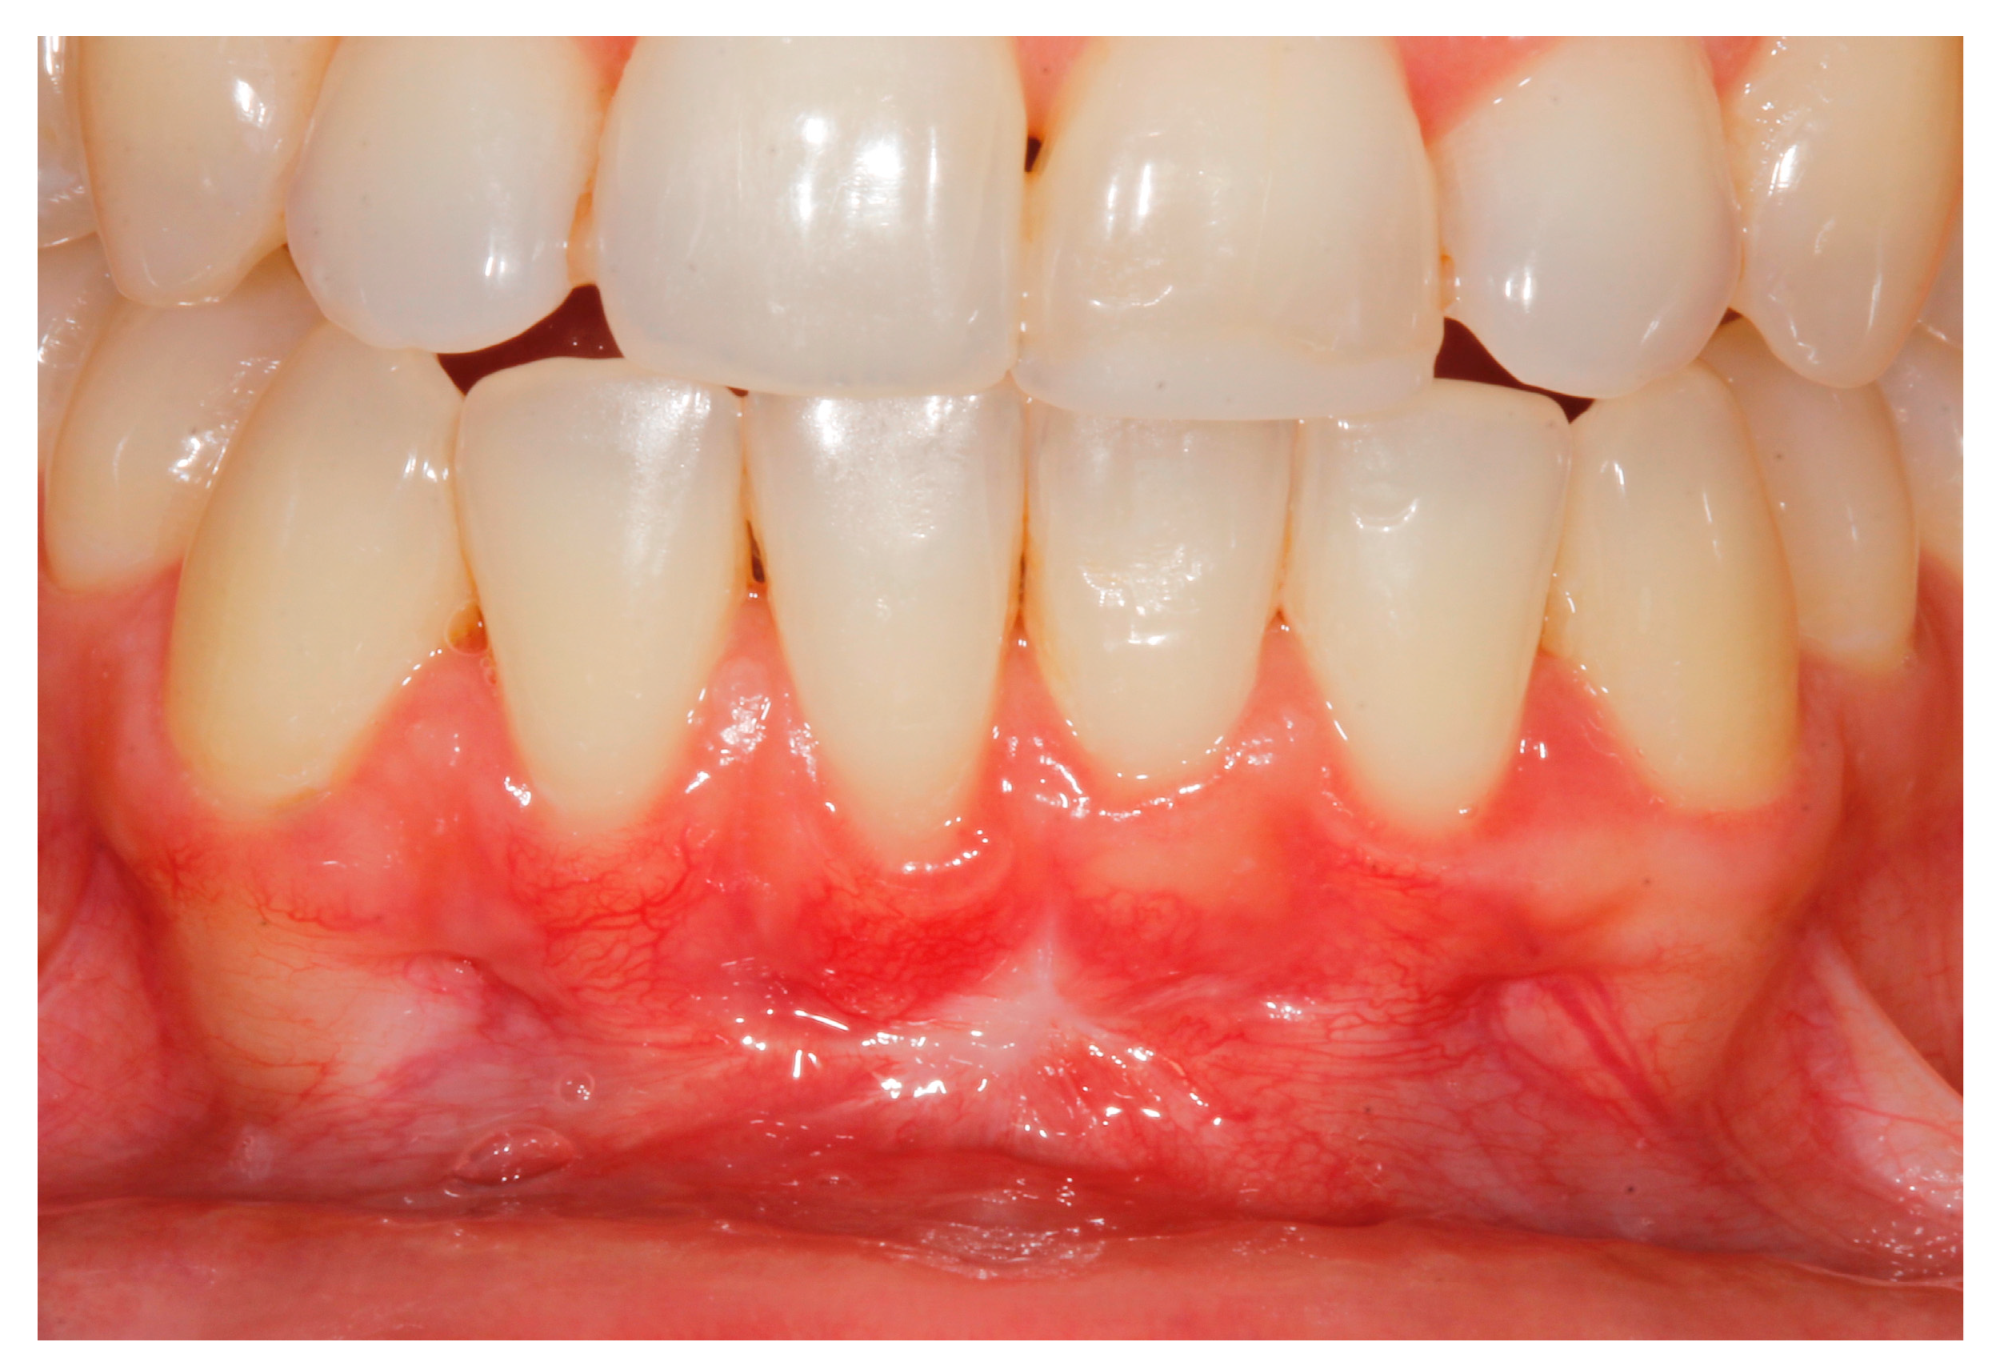

2. Case Study

- (a)

- deep partial thickness incision (blade parallel to the periosteum) made at the level of the external insertion of the frenulum;

- (b)

- elimination of superficial mucous tissue and muscle of the frenulum;

- (c)

- a series of detached points with periosteal anchorage for the apical positioning of the lining mucosa of the lip and the second intention healing of the exposed periosteum.